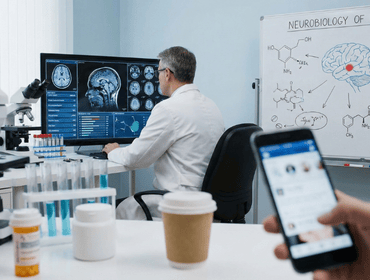

The Science of Addiction